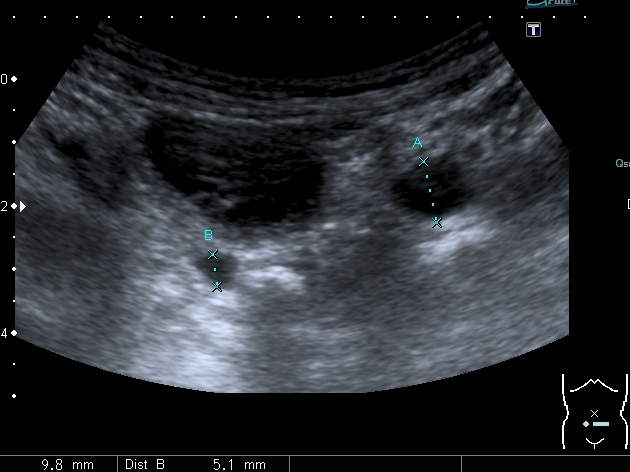

Ребёнок 4-х лет с терминальной гидроцефалией (объём мозгового черепа около 6 - ти литров на глаз), тетрапарезом, вторичным сколиозом 4-й степени, двухсторонним вывихом тазобедренных суставов, глуьокой умственной отсталостью поступил в детское хирургическое отделение. Мать отмечает в течение последних 2-х месяцев кровянистые выделения на памперсе, в последние несолько недель беспокойство ребёнка. В анализе мочи - гематурия.

Произведено УЗИ с бльшими техническими трудностями из - за сопутствующей ортопедической и неврологической патологии

Мочеточники в нижней трети

Нейрогенный мочевой пузырь (?), МКБ, конкремент мочевого пузыря, двухсторонний мегауретер, конкремент правой почки.

Если честно, и я изначально не совсем понял, где находится конкремент (а это конечно же конкремент), локализованный на урограммах. При первичном исследовании на УЗИ его я не видел (либо он спрятался за тенью конкремента мочевого пузыря, либо я обрадовался редкой находке конкремента такого размера в мочевом пузыре - 2.5 см, и не посмотрел что ниже). Тем не менее при ретроспективном анализе архивированных сонограмм, как мне кажется, он попал в один из сканов, м.б. не совсем чётко.

I20111114160229796.jpg

И всё -же, где конкремент :?:

Возможно, в дивертикуле либо в нижней трети мочеточника..

Верификация:

Выдержка из протокола операции- "...вскрыт мочевой пузырь, обнаружен камень 4 х 3х 2.5 см, плотный, удалён. При дальнейшей ревизии мочевого пузыря обнаружен вколоченный камень в шейке мочевого пузыря и в уретре, удалён камень 2 х 1.5 х 1.5 см. При осмотре устья левого мочеточника - последний зияет, мочеточник расширен до 1 см, учитывая расширение мочеточника, проведена антирефлюксная пластика по Грегуару..."